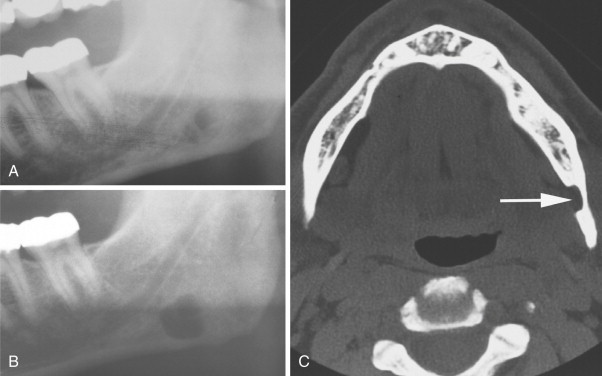

What is this radiolucency?

Stafne defect

*mandibular salivary gland surrounded by madnibular bone*